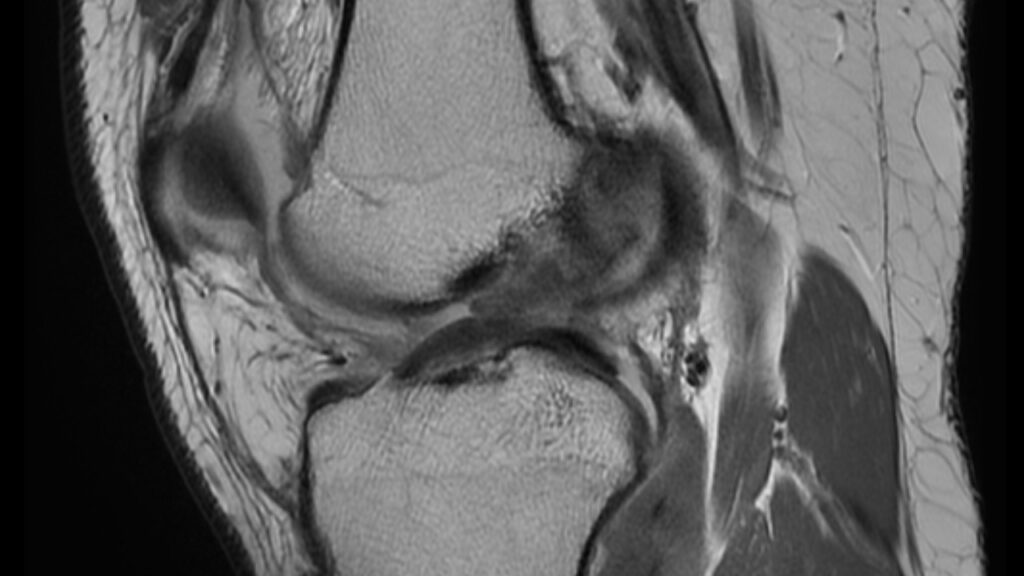

張先生立刻就醫,經過病史詢問和體格檢查後,醫生懷疑他可能有ACL撕裂。在進行前拉測試(Anterior Drawer Test)和拉赫曼測試(Lachman Test)後,結果均呈現陽性,顯示他的膝蓋不穩定。MRI檢查結果顯示,張先生的前十字韌帶部分撕裂,如下圖所示:

- 影像檢查:X光片可排除骨折,磁共振成像(MRI)則能更清楚地顯示韌帶的損傷程度。